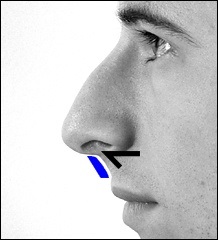

Mielőtt nagyobb acanthion. Ez az, amit úgy néz ki, a művelet során. Az ábrán a jobb ez sárga színű. Acanthion columella található, közvetlenül alatta, ahol a felső ajak határos az alapja az orrát.

Része a gerinc, amelyeket el kell távolítani jelzi a kék vonalon. Removal végezzük vésővel.

A fotó távoli nazális gerinc. On line távolság centiméterben, és a fekete nyíl képviseli a távolság egy inch.

Ebben a beteg, ott van a hatás a „kötés” a felső ajak. Photo fenti elégedett üzemeltetés előtt. Fekete jelzi a helyzetét az első kiálló orr-gerinc. A kék vonalat húzott a jobb megítélése a profilt. Ha a hatása „árukapcsolás” a felső ajak vonal irányította a profilját Vered és legfeljebb az alap az orr.